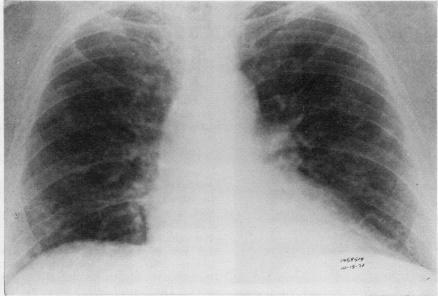

A case of multiple nodular pulmonary amyloidosis in a 54-year-old Caucasian man is presented. Discrete symptomless radiodensities had developed in this patient's lungs within a period of three years, leading to a suspicion of a neoplastic process. The amyloid nature of these nodules was demonstrated by biopsy. In this case, as in others previously reported, there was no evidence of systemic disease, and immunoglobulins were normal. Local factors probably play an important part in the pathogenesis of this disease. This entity is to be distinguished from the diffuse type of pulmonary amyloidosis, which has a far graver prognosis. Diffuse alveolar septal amyloidosis is usually associated with primary systemic amyloidosis or multiple myeloma and leads rapidly to respiratory distress.